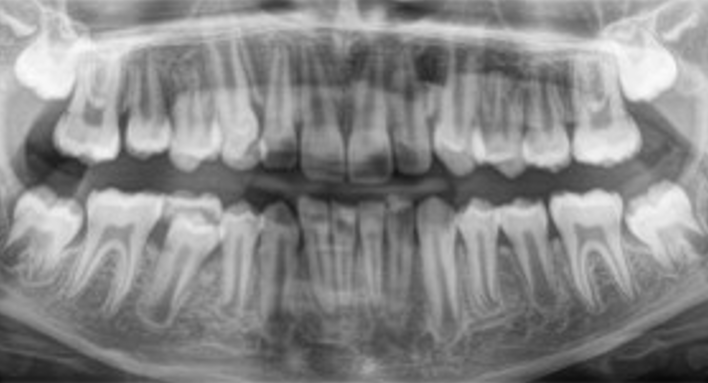

Панорамний знімок загальний (P1)

Ортопантомограма (ОПТГ) потрібен щоб:

• Оцінити стан зубів, коріння, каналів. А також побачити пломби, імпланти, коронки, проаналізувати структуру тканин пародонту.

• Виявити приховані запальні процеси, каріозні порожнини, патологічні утворення (кісту, абсцес).

• Виявити пародонтальні кишені.

• Провести оцінку стану навколозубних тканин, верхньощелепних синусів, скронево-щелепного суглоба.

• Визначити параметри щелепної кістки, положення, стан зубів у ряду, включаючи зуби мудрості.

• Хоча панорамний знімок — один з основних діагностичних інструментів стоматолога, він має деякі похибки:

• Геометричні спотворення, що не дають 100% точність зображення (корекція змін становить 20%).

• Навіть мінімальне зміщення щелепи обумовлює зміщення фокусної плями, через що зображення стає стисненим або розтягнутим.

• Через структурні відмінності у тканинах, що потрапили в зону дії рентгенівського випромінювання, щільні тканини не дають достовірно оцінити стан менш щільної губчастої кістки.

• Двовимірний знімок щелепи зубів не оцінює форму кісткового гребеня, структуру кістки на рівні, що цікавиться.

Ортопантомограма — це швидше допоміжний діагностичний інструмент, що надає оглядову картину і виявляє явну патологію. На відміну від панорамного знімка, 3D комп’ютерна томографія дає не одне плоске зображення щелепи. Лікар отримує низку послідовних зображень у різній проекції без спотворень, властивих панорамного знімка. Отримане тривимірне зображення дозволяє лікарю розглянути щелепно-лицьову зону на будь-якій глибині з усіх боків та кутів. Приклад: на панорамному знімку видно правильний імплант, а на КТ дослідженні виявлені помилки при встановленні.